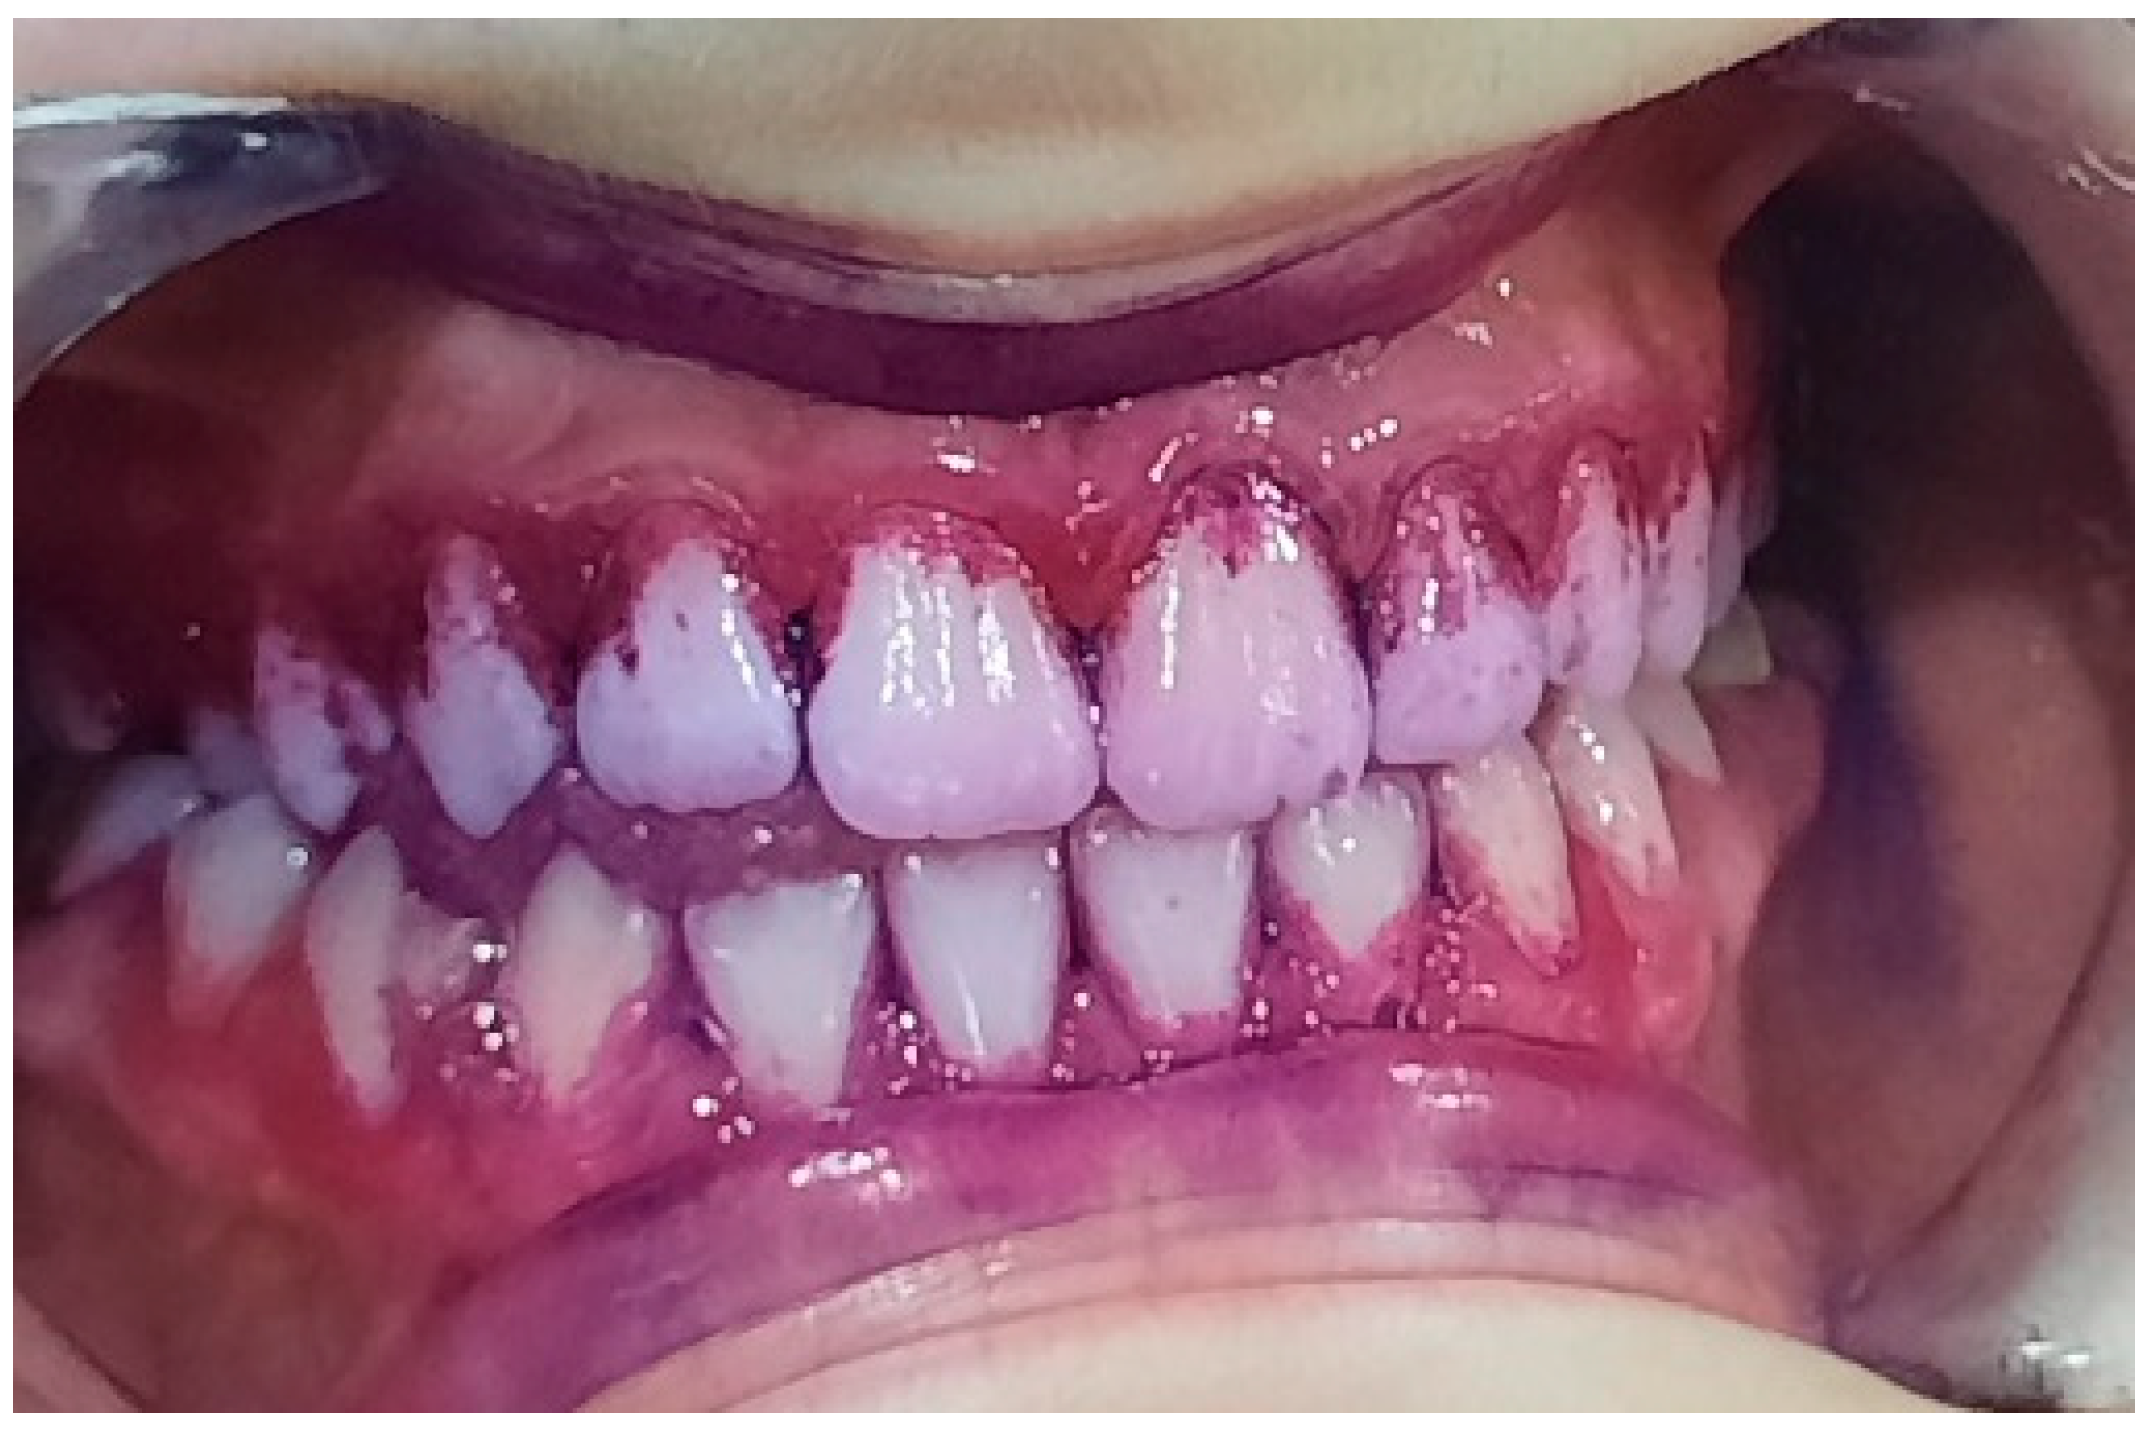

2.2. Clinical Examinations

3.2. Analysis of Clinical Data

| Gingival Index | |||||||||

| Gums with Normal Appearance (Cod 0) | Gums with Mild Inflammation (Cod 1) | Gums with Moderate Inflammation (Cod 2) | Gums with Advanced Inflammation (Cod 3) | ||||||

| Groups | N | T1 | T2 | T1 | T2 | T1 | T2 | T1 | T2 |

| all | 62 | 0 | 51 | 26 | 9 | 23 | 2 | 13 | 0 |

| group A | 31 | 0 | 23 | 9 | 6 | 11 | 2 | 11 | 0 |

| group C | 31 | 0 | 28 | 17 | 3 | 12 | 0 | 2 | 0 |